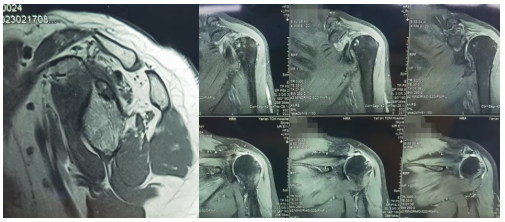

术前评估:巨大肩袖撕裂,Goutallier2 级

术前详细查体、评估影像学资料,发现此例患者为可修复巨大肩袖撕裂,运动医学科团队在术中充分松解关节间隙后运用 Mason-Allen 减张双排缝合技术修复肩袖,探查肩袖修复强度可靠。